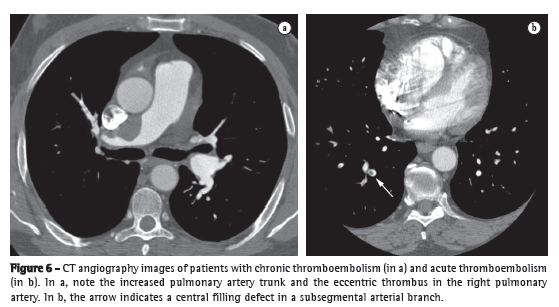

Chest X-ray changes are seen in more than 85% of patients with a confirmed diagnosis of PH.(4) The major changes found include increased pulmonary artery diameter at the hilar level, in 78% of cases (Figure 1); peripheral tapering of vessels, in 62%; and hyperlucent lung periphery, in 9% (Figure 2). The pulmonary artery diameter at the hilar level can be determined by measuring the interlobar artery diameter. The maximum transverse diameter of the right interlobar artery, as measured from its lateral aspect to the air column of the intermediate bronchus, is 16 mm in men and 15 mm in women.(5) Because of the difficulty in assessing the left pulmonary artery by posteroanterior chest X-ray, the vessel should be assessed by lateral X-ray, beginning at the circular transparency created by the left upper lobe bronchus (which is visualized as being telescoped) and extending to the posterior margin of the vessel saddling the bronchus (Figure 1). The maximum limit of normality is 18 mm. A hilar-thoracic index (sum of the diameters of the pulmonary hila divided by that of the chest) above 38% is classically described, being present in approximately 75% of patients with PH (Figure 1).(6) Vascular calcification, usually located in the pulmonary artery trunk (PAT) or in its hilar branches, is rarely detected. This change is most commonly associated with congenital heart diseases and chronic central embolism.

Chest X-ray can facilitate the differential diagnosis with pulmonary parenchymal disease, heart failure, COPD, and kyphoscoliosis, as well as raising the suspicion of pulmonary thromboembolic disease when there are findings of oligemia, multiple areas of consolidation suggestive of pulmonary infarction, or asymmetry among the major pulmonary arteries (Figure 2).(7)